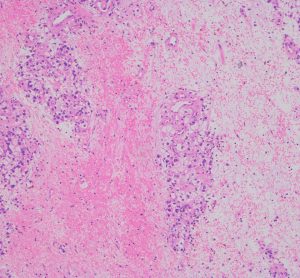

左側頭葉への腎癌の単発転移です。症候性てんかん(失語症発作)で発見され,定位放射線治療を受けたのですが,数ヶ月後に脳浮腫が高度となり失語症が悪化しました。コアになっている円形の転移腫瘍の周囲に放射線による脳壊死を疑いました。2時間ほどの開頭手術で,右側のガドリニウム増強されているところだけを摘出しました。

腫瘍中心の壊死の部分です。腫瘍細胞が死滅して凝固壊死の像です。血管はヒアリン化して閉塞しています。

腫瘍の辺縁部で手術中に血管が発達して出血があった部分です。腫瘍細胞 clear cell carcinoma が新生血管周囲に増殖しています。真ん中はPAS染色,右側はMIB-1染色で13%くらいの高い陽性率です。これは定位放射線治療で腫瘍が全部死滅していなくて一部では再発していることを示します。

さらに周辺と正常脳との境界部位です。脳組織が壊死になっていてます。放射線脳壊死が周囲にあって,高度の脳浮腫を生じていたことがわかりました。

この例は,定位放射線治療後に,1) ガン組織が壊死になって放射線治療の効果が認められる,2) ガン転移の再発がある,3) 放射線脳壊死が起こっている,という3つの事象が混じって生じているものです。ですから,PETやMRSなどで手術の前の画像診断を頑張ってみても,診断がつくはずがないのです。病理診断しか手段がありません。

手術1年半後の画像です。症状はなくて元気にお暮らしでした。新たな脳転移はありません。